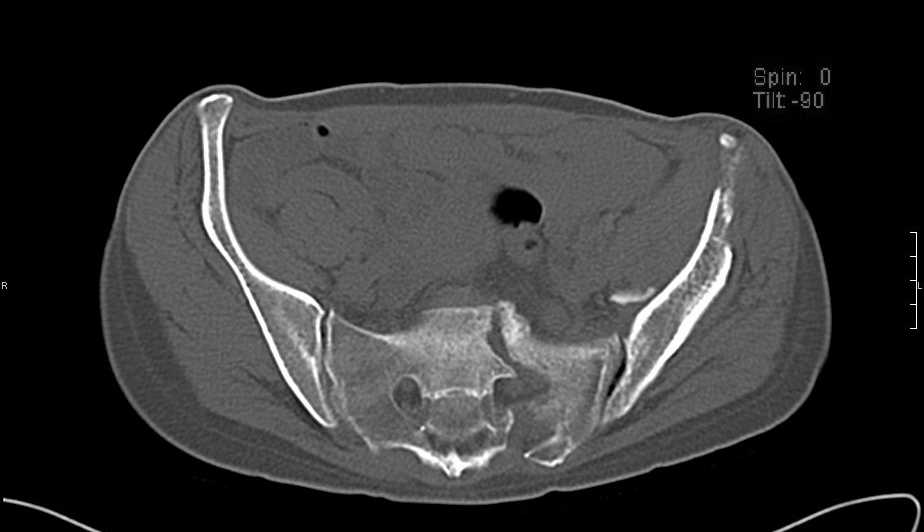

Больная 43 года (промышленный альпинист), 28.07.08 в результате падения с 5 этажа получила политравму:

Перелом свода и основания черепа. Вертикально-нестабильное повреждение таза, осложнённое разрывом мочевого пузыря. Чрезвертельный перелом левого бедра. Перелом правой таранной кости, переломовывих правой кубовидной кости. Тупая травма живота, разрыв печени, ушиб почек. Забрюшинная гематома. В день травмы - лапаротомия, ушивание ран печени. Разрыв мочевого пузыря не диагностирован. Течение болезни осложнилось развитием мочевого затёка и обширной пред- и забрюшинной флегмоны, сформировался свищ мочевого пузыря. 19.8.2008 вскрытие, дренировние флегмоны, ревизия мочевого пузыря, обтурация мочевого свища (свищ закрылся в октябре), 1.10.2008 некрэктомия, пластика по Шеде-Лидскому правой кубовидной кости. По результатам КТ диагностирован рак правой почки (диагностическая находка), 8.10.2008 нефрэктомия справа.

Имеется вертикальное смещение левой половины таза с выраженным отведением крыла (клинически подвижности нет), несросшийся низкий двухколонный перелом левой вертлужной впадины с потерей конгруэнтности, укорочение около5 см, застарелый разрыв лонного сочленения, неправильно сросшиеся переломы обеих ветвей правой лонной кости с укорочением, патологическая подвижность лоно-седалищного фрагмента слева. Правая нижняя конечность неопорна, несмотря на то, что лежа прямую ногу поднимает, ходит на левой ноге (ортопедическая обувь) с костылями, справа тазобедренный ортез. Седалищные нервы работают.Урологи отпустили больную на 6 мес.